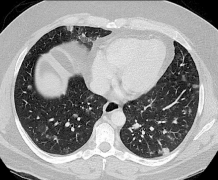

经皮肺穿刺活检并发症:血胸

81岁女性患者行CT引导下右上肺叶肿块肺活检。 18g半自动同轴针三次取样。 穿刺完成时CT显示肺泡出血,患者出现轻微咯血。 病人住院进行监护。一般情况下在协和医院大多数肺活检是在门诊进行的,监测时间1-2小时。 患者4小时后出现低血容量性休克,这是肺活检...